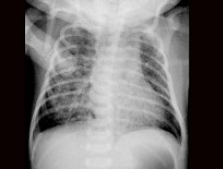

患儿,男,1天,生后呼吸困难,羊水见胎粪污染,如图,最可能的诊断为()

A.新生儿肺炎

B.新生儿湿肺

C.新生儿肺出血

D.新生儿呼吸窘迫综合症

E.胎粪吸入综合征